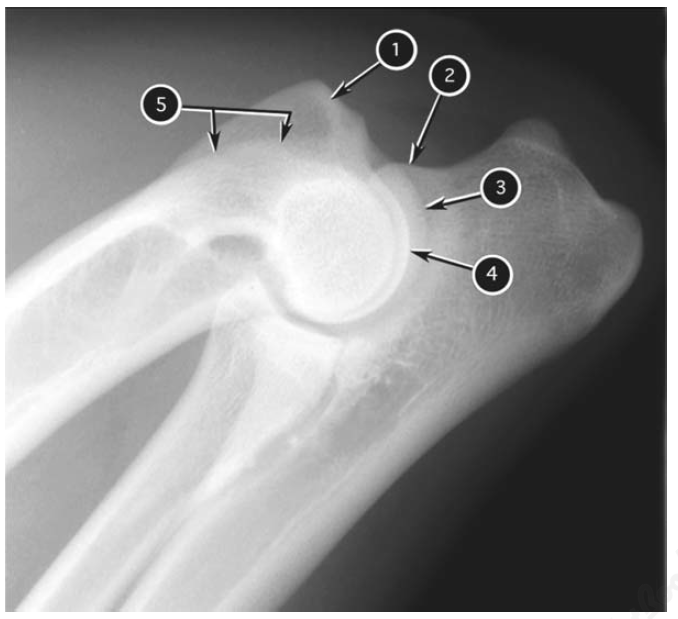

Flexed mediolateral radiograph of canine elbow joint

What number?

- Anconeal proces of ulna

- Medial part of humeral condyle

- Lateral part of humeral condyle

- Medial epicondyle of humerus

- Caudal border of lateral epicondyle of humerus

A

1. Medial epicondyle of humerus

2. Anconeal proces of ulna

3. Medial part of humeral condyle

4. Lateral part of humeral condyle

5. Caudal border of lateral epicondyle of humerus